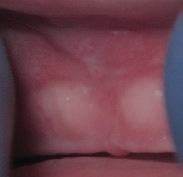

There Is Only One Smile That Matters. Yours!

You are in good hands! Dr. Makarita is the only accredited Fellow of the American Academy of Cosmetic Dentistry in Virginia.

BEFORE AFTER

At Tysons Aesthetic Dentistry Dr. Makarita has designed and equipped his practice with your smile in mind. Dedicated care and attention are just the beginning.

As a general dentist with a passion for aesthetic and cosmetic dentistry, whether a simple filling or a smile makeover, Dr. Makarita’s priority is to help you love your smile.

Since earning his doctorate from the Medical College of Virginia, Dr. Makarita has continually upgraded his skills and knowledge with continuing education so he can always bring you the most advanced options for all your dental needs.

Always welcoming new patients! Call 703-532-2020  8150 Leesburg Pike | Suite 503, Vienna VA 22182 www.ilovethatsmile.com

FREE SMILE EVALUATION In person or visit website for virtual smile consultation

Dr. H.R. Makarita

Accredited Fellow, American Academy of Cosmetic Dentistry

Master, Academy of General Dentistry

Master, International Congress of Oral Implantologists

Master, Las Vegas Institute for Advanced Dental Studies

to Love Your Smile? Dr. Makarita would love to meet you! About